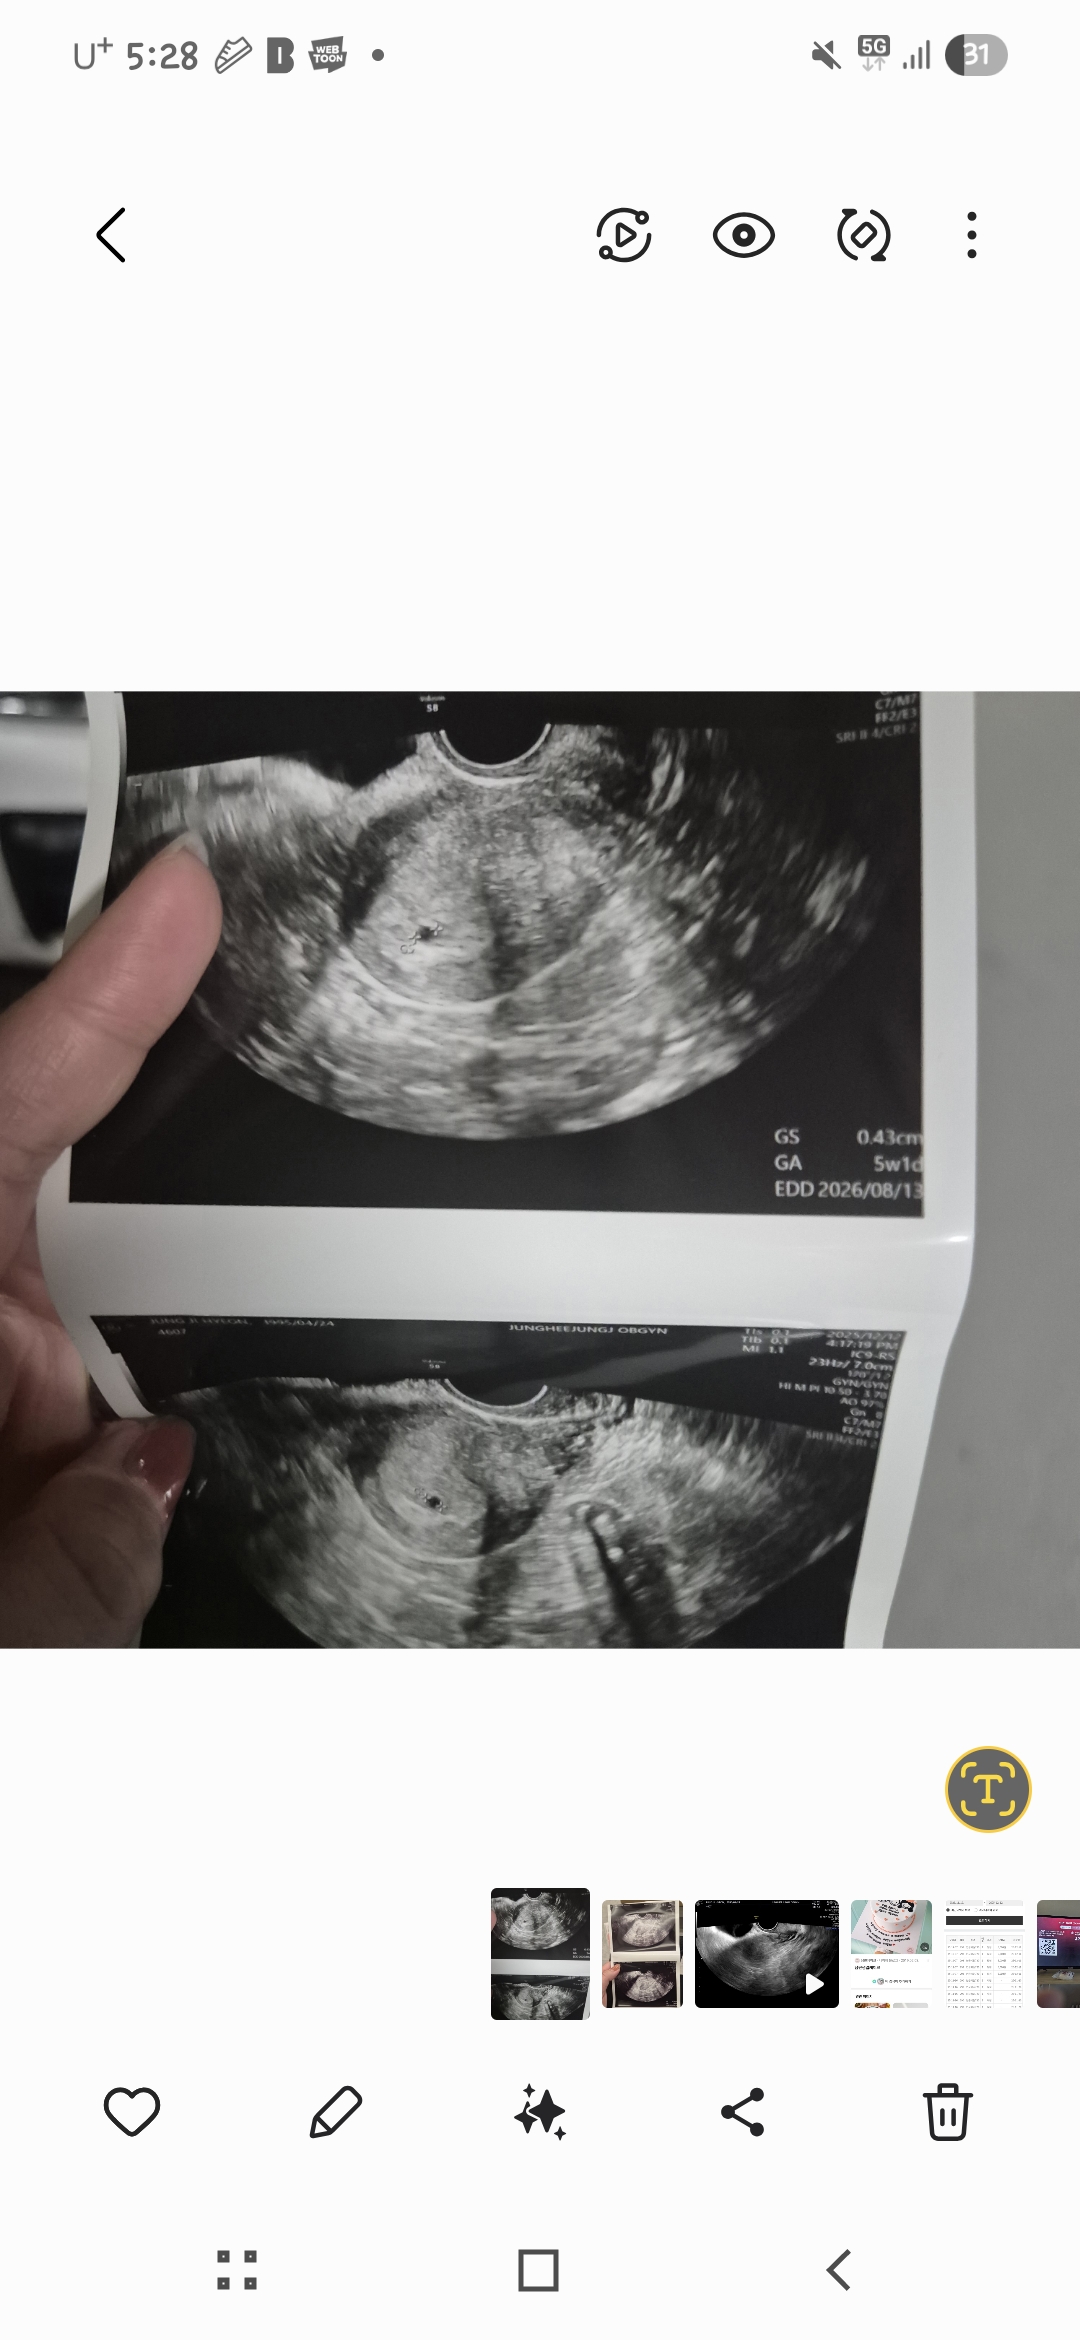

배란 19일차인 12/8 월요일 아기집 0.29cm 확인하고 일주일뒤에 오라고하셨는데 못참고 오늘 (12/12) 다녀왔어요. 0.43이라고하셨고 5주 1일차 라고해주셨어요.. 너무 자라는게 더딘건 아닌지 걱정되고 2주뒤에 오라고하시는데 심소들을수있을지 너무 걱정이네요..임신만 하면 되는줄알았는데 산넘어 산.. 4일뒤에 이정도 자라도 괜찮을지..선생님은 너무 괜찮다하시는데 마음이 놓아지질않네요ㅠㅠ